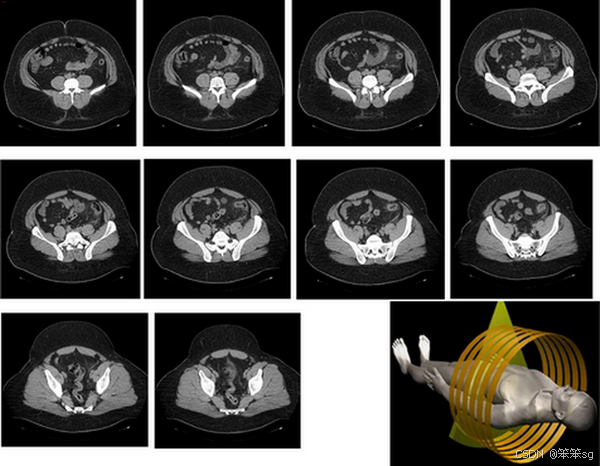

3. 3D卷积(体数据)

- 输入数据:3D数据,如CT扫描生成的立体图像,形如

14×14×14,代表长、宽、高。 - 卷积操作:使用3D过滤器,例如

5×5×5,在长、宽、高三个维度上滑动,检测3D特征。输出形如10×10×10。 - 多通道和多过滤器:如输入带有多个通道(如不同的CT扫描片段)并使用16个过滤器,输出将是

10×10×10×16。 - 应用场景:3D卷积主要用于处理体数据,如医疗影像中的CT、MRI扫描,以及视频分析(如动作识别),将时间作为第三个维度。